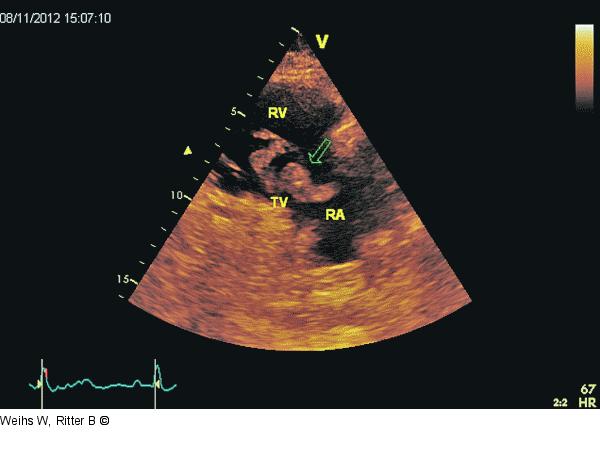

Abbildung 2: Rechtsventrikulärer Einflusstrakt Parasternale Darstellung des rechtsventrikulären Einflusstraktes. Flottierender Thrombus (Pfeil) im RA. Dilatierter und hypokontraktiler RV. RA: rechter Vorhof; RV: rechter Ventrikel; TV: Trikuspidalklappe. |

Parasternale Darstellung des rechtsventrikulären Einflusstraktes. Flottierender Thrombus (Pfeil) im RA. Dilatierter und hypokontraktiler RV. RA: rechter Vorhof; RV: rechter Ventrikel; TV: Trikuspidalklappe. |